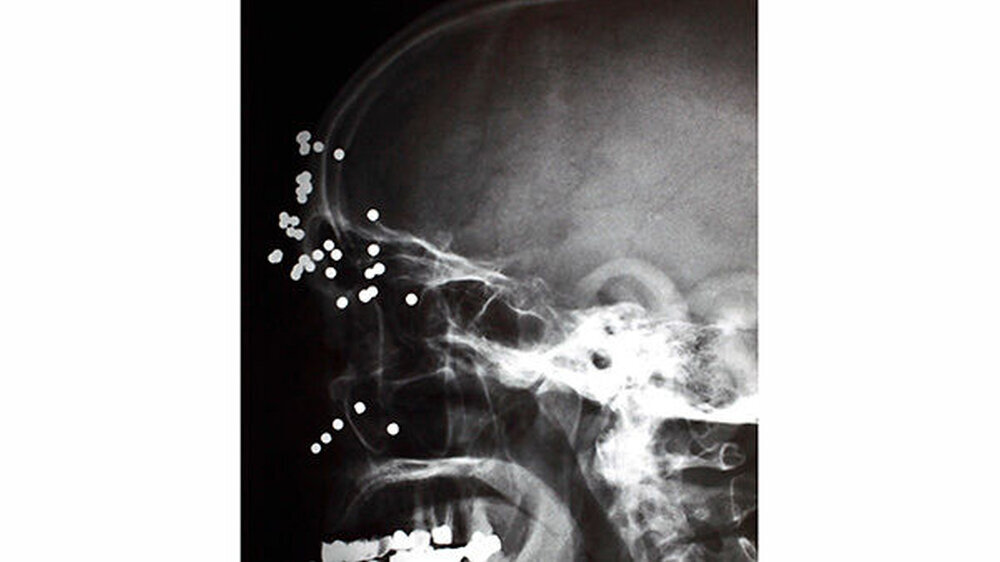

Fremdkörper im Gesicht

Vom Bohrer im Kopf bis zum Schlüssel in der Kieferhöhle: Die MKG-Chirurgen der Charité haben ausgewählte Patientenfälle mit Fremdkörpern im Gesicht zusammengestellt. In unserer Fotostrecke finden Sie die eindrucksvollen Aufnahmen.